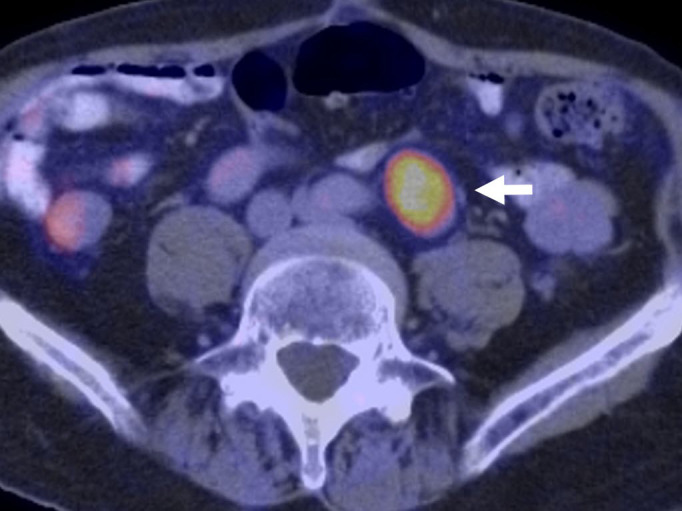

Materials: we present the case of an 82-year-old male patient with a recent diagnosis of moderately differentiated adenocarcinoma of the colon and a hypermetabolic periaortic nodule as an incidental finding.

Results: percutaneous biopsy of the periaortic nodule confirmed the diagnosis of schwannoma. At one year of follow-up, growth of the schwannoma has been demonstrated. There are no signs of progression of his oncological disease.

Conclusions: schwannomas are benign tumors, rarely found in the retroperitoneum and can be sources of false-positive positron emission tomography results.